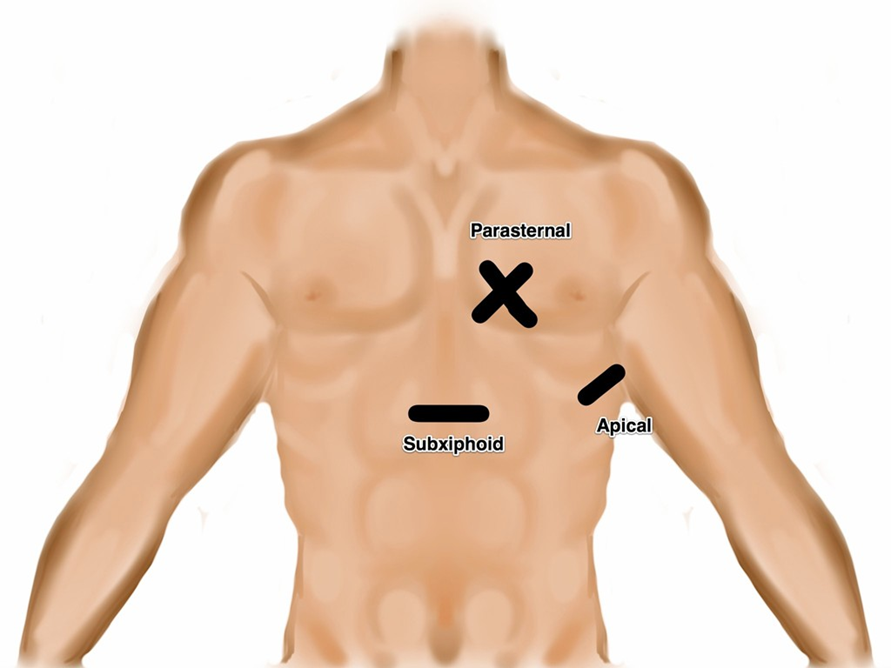

- Illustration 1. Transducer location for the four focused cardiac views

- Subxiphoid or Subcostal View: The liver is used as an acoustic window and is seen at the left of the screen and near field. The right ventricle being the most anterior is adjacent to the liver. The apex will be to the right of the screen. By fanning inferiorly, the inferior vena cava (IVC) is seen in short axis. Often the hepatic veins can be seen in the liver draining into the IVC.

Video 1. Normal Subxiphoid View - Parasternal Long Axis View: This view captures the flow of blood through the left side of the heart. The apex is to the left of the screen. The mitral valve leaflets are seen and often chordae tendinae connecting them to papillary muscles. Two cusps of the aortic valve (usually the non-coronary and right coronary cusp) are seen. The left ventricular outflow tract (LVOT) is the term for the aortic root and proximal ascending aorta. A portion of the right ventricle is seen in the near field.

Video 2. Normal parasternal long axis view - Parasternal Short Axis View: This view is a cross sectional view of the left and right sides of the heart. These can be “sliced” at various levels between the base and the apex. By fanning the probe towards the right shoulder, one can visualize the aortic valve in cross section. The “Mercedes Benz” sign shows all three of the leaflets. The right ventricular outflow tract and pulmonary valve can be seen in this view. At the base, the mitral valve is seen inside the left ventricle. At the mid ventricular level, the papillary muscles are seen within the left ventricle. This is the most commonly used parasternal short axis view in point-of-care ultrasound in the acute care setting. At the apex, the left ventricle has tapered and no structures are seen within.

- Apical Four Chamber View: This view shows all four chambers of the heart. The apex is toward the near field with the interventricular septum pointing to approximately the 12 o’clock position. By fanning superiorly, the apical five chamber view can be obtained, with the “fifth chamber” being the LVOT with the aortic valve.

- Subxiphoid or Subcostal View: The liver is used as an acoustic window and is seen at the left of the screen and near field. The right ventricle being the most anterior is adjacent to the liver. The apex will be to the right of the screen. By fanning inferiorly, the inferior vena cava (IVC) is seen in short axis. Often the hepatic veins can be seen in the liver draining into the IVC.